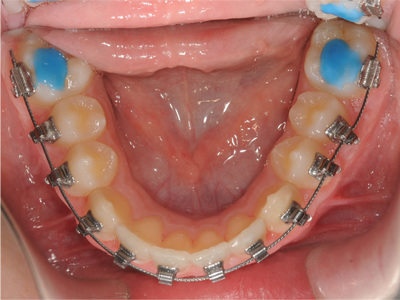

Class I Non-Extraction |